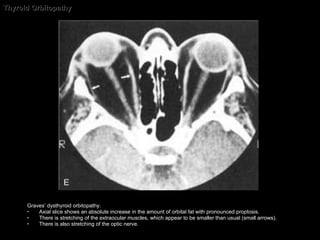

Thyroid Orbitopathy Graves’ dysthyroid orbitopathy.  Axial slice shows an absolute increase in the amount of orbital fat with pronounced proptosis.  There is stretching of the extraocular muscles, which appear to be smaller than usual (small arrows).  There is also stretching of the optic nerve.